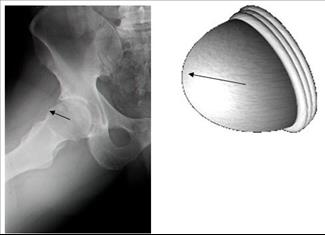

ארתרוסקופיה של מפרק הירך

מאת: ד"ר דוד מורגנשטרן 19/05/2014

מאת: ד"ר דוד מורגנשטרן 19/05/2014מפרק הירך הוא המעוז האחרון שנכבש על ידי הניתוחים הארתרוסקופים. הברך, הקרסול, הכתפיים, מרפק ושורש כף היד - מנותחים ב... לכתבה המלאה